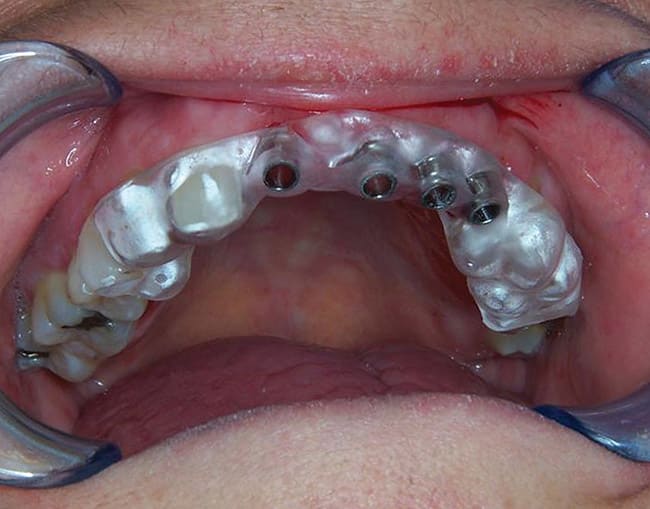

The primary author developed the Fabricated Implant Restoration and Surgical Technique (F.I.R.S.T.®) (Patent: USPTO #7,108,511 B; September 2006), which enables the placement of mini dental implants and permanent crowns to be cemented in a single visit (Figure 11 through Figure 15).